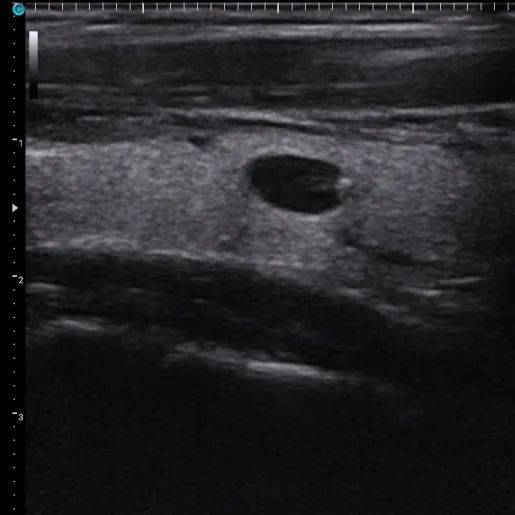

01、看数目

1. 单发结节:甲状腺内只有一个结节。

2. 多发结节:甲状腺内不只一个结节。

单发结节和多结节超声图像